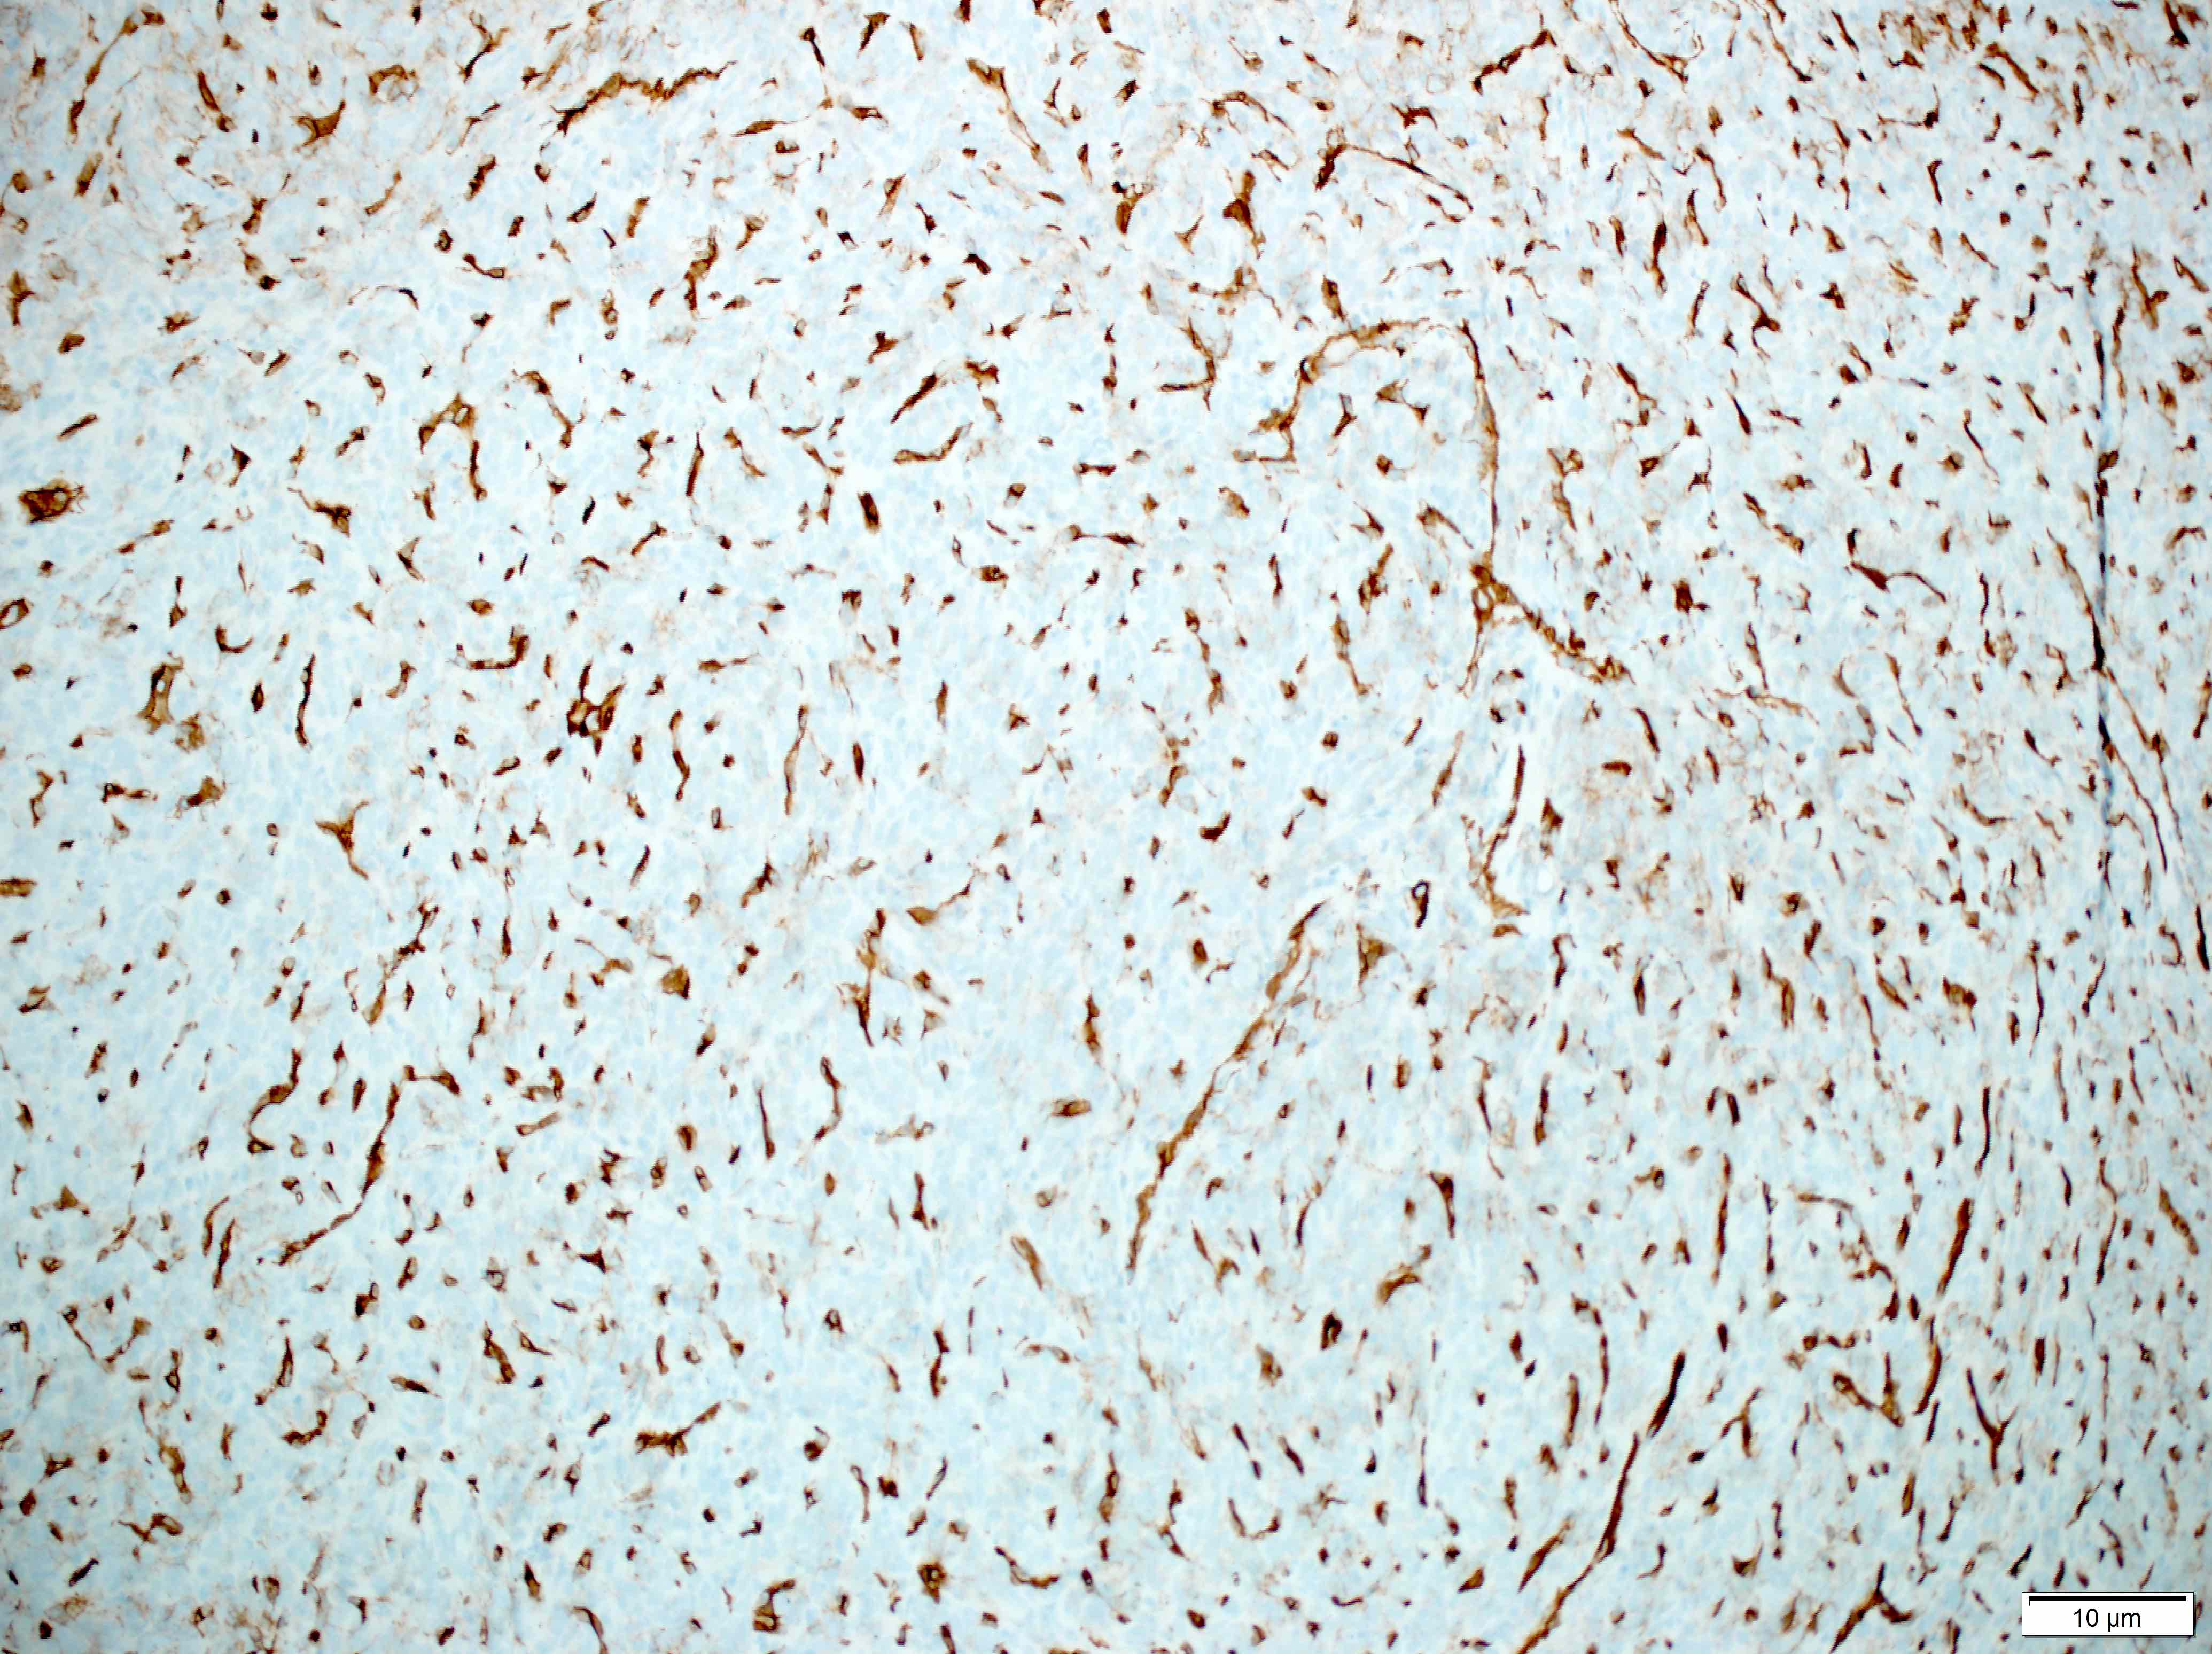

Positive stains

- CD34 (lost in some high grade tumors) (Am J Surg Pathol 1997;21:1354)

- STAT6 (nuclear, lost in some dedifferentiated tumors) (Int J Surg Pathol 2017;25:58)

- Vimentin

- CD99

- SMA (tumor periphery)

- BCL2

Microscopic (histologic) images